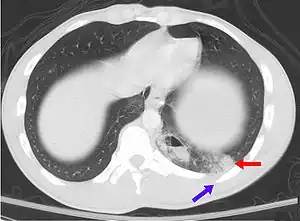

| A CT scan showing a pulmonary contusion (red arrow) accompanied by a rib fracture (blue arrow) | |